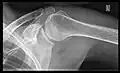

- Y-projection

The lateral contour of the shoulder should be positioned in front of the film in a way that the longitudinal axis of the scapula continues parallel to the path of the rays. This method reveals:[24]

- The horizontal centralization of the humerus head and socket

- The osseous margins of the coraco-acromial arch and hence the supraspinatus outlet canal

- The shape of the acromion

This projection has a low tolerance for errors and, accordingly, needs proper execution.[24] The Y-projection can be traced back to Wijnblath’s 1933 published cavitas-en-face projection.[25]

Y-projection conventional radiography